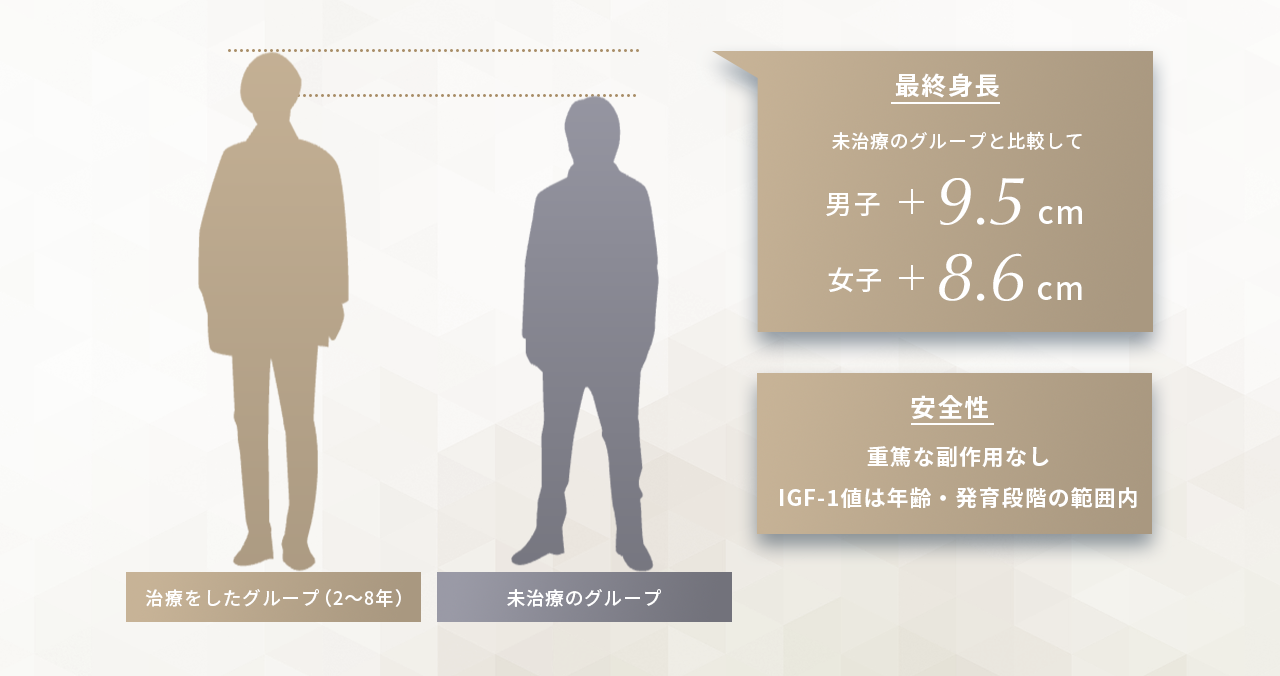

成長ホルモン療法は、体内のホルモン分泌や働きが不十分な場合に、外部から成長ホルモンを補充し、骨端線の活性を促進する医療手段です。かつては主に保険適用の限られた疾患に対して行われていましたが、現在では特発性低身長(ISS)や家族性低身長など、明確な病因のないケースにも自由診療として選択肢が広がりつつあります。

国際共同研究(The Journal of Clinical Endocrinology & Metabolism)では、特発性低身長の小児に高用量投与を行った結果、未治療群に比べ男子で平均+9.5cm、女子で+8.6cmの最終身長増加が確認されました。副作用は軽微で、安全性も概ね良好と報告されています。

当院では、このように科学的根拠・安全性が証明された治療法を採用しています

Sotos JF, Tokar N. Growth hormone significantly increases the adult height of children with idiopathic short stature: comparison of subgroups and benefit. Int J Pediatr Endocrinol. 2014;2014(1):15. doi:10.1186/1687-9856-2014-15.